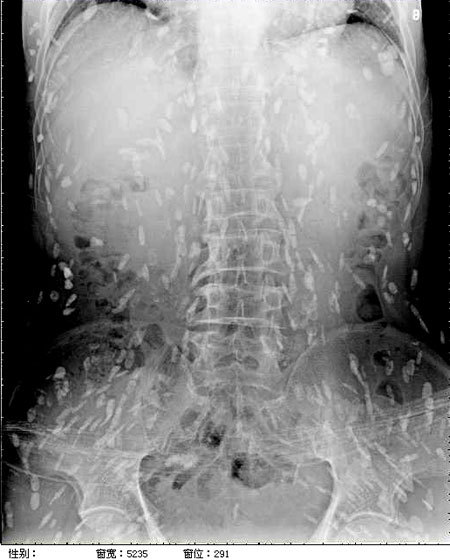

엑스레이를 찍어보니, 온몸에 촌충 같은 기생충이 퍼져있는 것이 Xray사진에 찍혔다.

기침으로 인한 고통을 호소한 환자를 진료하던 의료진은 환자의 엑스레이 사진을 보고 경악했습니다. 엑스레이 촬영물에는 여러 마리의 촌충과 유충이 가득 찍혀있는 것이었습니다.

브라질의 한 의료진이 소셜네트워크서비스(SNS)에 기생충에 감염된 엑스레이 사진을 공개했습니다. 사진에는 몸속에 있는 기생충이 죽어 석회화된 수백 개의 점 형상이 보였습니다.

특히 유충이 근육이나 뇌 조직에 침투한 모습은 매우 충격적이었습니다. 이러한 증상은 유구조충의 유충에 의한 인체감염증으로, 유구 낭미충증이라고도 불립니다.

유구낭미충증은 주로 인간의 장에 사는 촌충의 유충이 근육이나 뇌로 침투할 때 발생합니다. 이 유충은 근육과 뇌에서 낭종과 같은 결절을 형성하기도 합니다.

의료진은 해당 환자가 특별한 치료를 받지 않았다고 밝혔습니다. 그는 "머리, 척수, 눈에 이상이 없는 한 치료가 필요하지 않습니다"라며 "해당 물체들은 석회화되어 있어 생존 가능한 유충이 아닙니다. 불편함을 느끼지 않는다면 특별한 조치가 필요하지 않습니다"라고 말했습니다. 그러나 해당 환자의 뇌에 낭종이 있는지 확인하기 위해 MRI 검사를 기다리고 있다고 전했습니다.